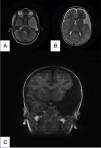

La aparición de un higroma subdural tras la rotura de la pared de un quiste aracnoideo es extremadamente infrecuente. Existen muy pocos casos descritos en la literatura. La mayoría de los casos se deben a una causa traumática. Su abordaje terapéutico, en aquellos casos sintomáticos, es controvertido, con una tendencia en la actualidad hacia el manejo conservador de forma inicial. En aquellos casos que precisen tratamiento quirúrgico existen múltiples opciones terapéuticas: se recomiendan las técnicas de fenestración como primera opción. Describimos 2casos tratados en nuestro centro, junto con una revisión de la literatura.

The appearance of a subdural hygroma after the rupture of an arachnoid cyst wall is extremely rare, with very few cases described in the literature. Most cases are due to a traumatic cause. The therapeutic approach in symptomatic cases is controversial, with a current tendency toward conservative management initially. In those cases that require surgical treatment, multiple therapeutic options are available, with fenestration techniques being recommended as first-line treatment. We describe 2cases treated in our centre and review the literature.